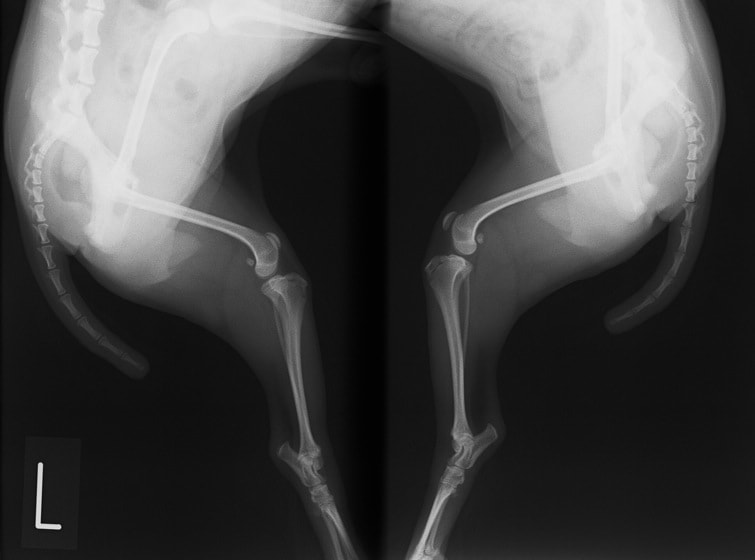

■ 症例24 キャバリア 7か月

左右膝蓋骨内方脱臼(左:グレードⅣ 右:グレードⅢ)

以前から左右後肢の跛行が認められ、整形外科学的検査・レントゲン検査により左右の膝蓋骨脱臼が認められた。症状が重度である左膝の膝蓋骨脱臼整復術を行った。外科手技は縫工筋及び内側広筋の解放、脛骨粗面の外側転位、滑車ブロック形造溝術、内外側関節方の縫縮を実施した。術後一か月時点で、左の膝蓋骨は安定しており経過は良好である。

本症例は成長期における重度の膝蓋骨脱臼であり、術後の再発の可能性もあるため、経過をしっかりと観察していく必要がある。また、今回手術を実施していない右膝に関しても経過を観察し、手術を検討していくこととする。